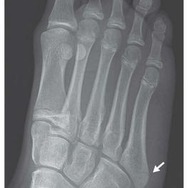

折れてしまったのは「中足骨」という足の中程にある骨。

足の指と足を繋ぐ骨で、細く弱いため比較的折れやすいことでも知られているそうです。

彼女の場合は右足の外側の中足骨の基部が折れてしまっており、松葉杖をついての通院治療が行われました。バランスが崩れた際に筋肉が激しく骨を引っ張ったことが原因ではないかと報告されています。